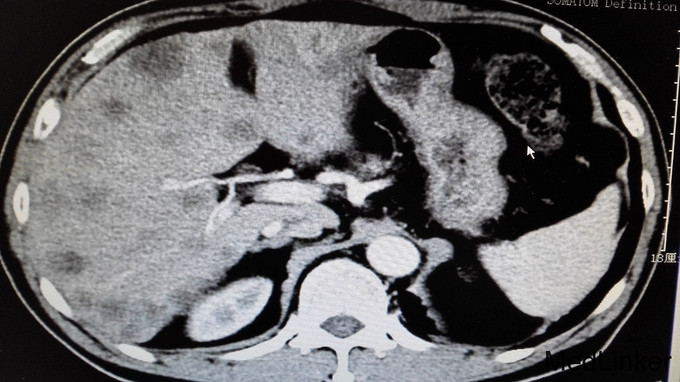

体格检查无特殊,未见明显阳性体征。 进一步完善辅助检查: 尿常规、大便常规、胸片、肝肾功能、血糖、血沉、风湿三项大致正常。血常规:白细胞11.7 ×10 9/L。右小腿MRI:1、右踝周围软组织信号改变,考虑炎症,请结合临床,必要时增强检查。2、右踝关节腔少许积液。血常规、心肌酶、电解质正常,心电图、心脏彩超未见明显异常。腹部CT平扫:1、肝实质多发稍低密度影性质待定,考虑转移瘤,建议进一步检查。2、肝左叶、尾叶多发低密度影性质待定,考虑囊肿。3、胆囊摘除术后。4、主动脉及右冠状动脉局部管壁钙化。AFP、CA199正常,CEA:6256.85ng/ml。输血前四项全阴性。全腹部增强CT提示:1、胃窦壁增厚,肝实质多发稍低密度影,考虑胃CA并肝内转移瘤可能,建议胃镜检查。2、肝左叶、尾叶多发囊肿。3、胆囊摘除术后。4、左肾囊肿。5、右肺下叶感染;左肺下叶纤维化病灶。6、主动脉及右冠状动脉局部管壁钙化。行胃肠镜检查提示慢性浅表性胃炎和盲肠占位,占位大小约40mm,已取病检。病检结果提示:盲肠中分化腺癌。

诊断:1、盲肠中分化腺癌并肝脏多发转移;2、右小腿软组织感染。 告知患者病情,目前无手术治疗指征,转肿瘤科行以化疗为主的肿瘤综合治疗。 患者经过再三考虑后,转省肿瘤医院消化肿瘤内科继续治疗。